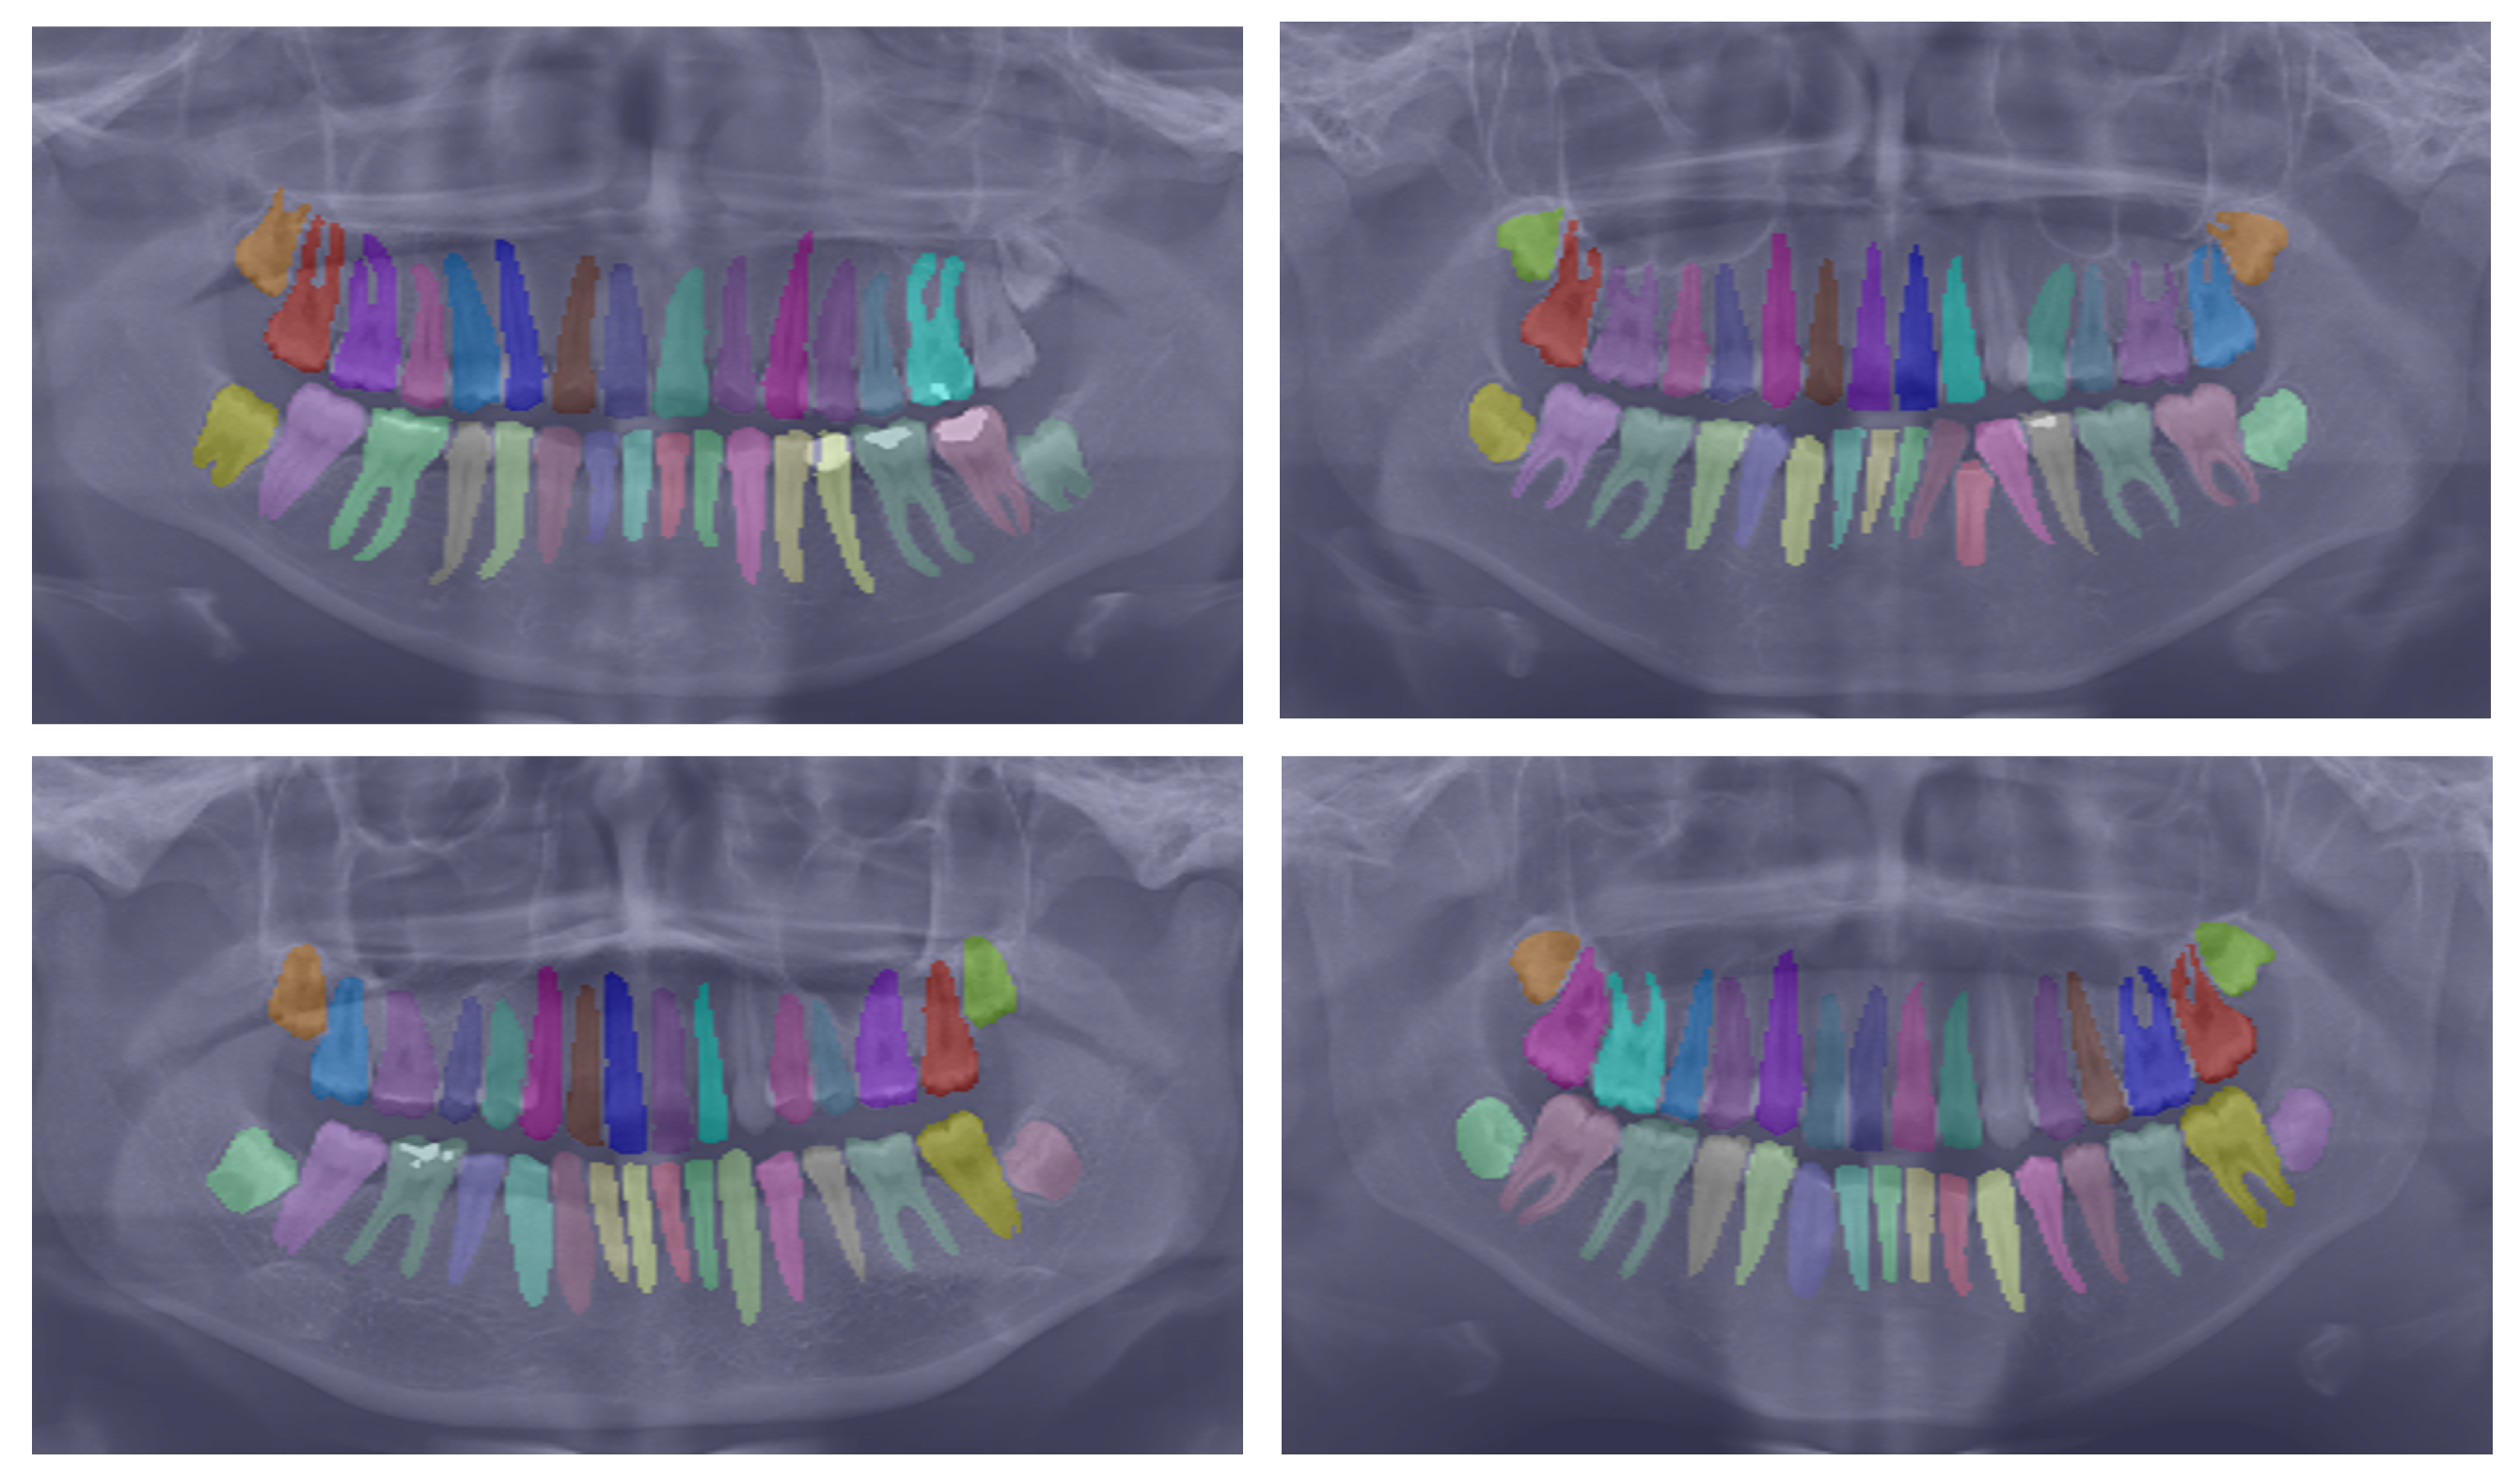

We evaluate the performance of our proposed network on the UFBA-UESC Dental Images dataset. Our analysis includes both quantitative and qualitative assessments, comparing our results to those of other state-of-the-art techniques. This section provides a comprehensive discussion of our evaluation results. Figure 3 presents a visual comparison of instance segmentation results produced by various networks (i.e., PANet, HTC, Mask R-CNN, ResNet, and our approach) alongside the ground truth.

Figure 3.

Comparison of teeth instance segmentation results for various networks—PANet, HTC, Mask R-CNN, ResNet, and our proposed approach—alongside the ground truth.

To further substantiate our comparison, we visualized the results from our proposed model. Figure 3 displays the instance segmentation results of various networks compared to the ground truth. Our method demonstrates closer alignment with the ground truth, indicating better performance in teeth instance segmentation tasks compared to the other methods. Notably, our proposed network maintains a consistent performance across all teeth, unlike the other networks. The synergistic benefits of the two tasks, SS and affinity pyramid, primarily drive the improvement in instance segmentation performance. Figure 4 depicts the results of panoptic segmentation with the background class (semantic segmentation) and tooth classes (instance segmentation). Figure 5 presents the precision–recall curve, which is the average of precision and recall for all classes. Panoptic segmentation improves the Dice score by also considering the surrounding tissues of teeth; thus, the loss also takes into account the background segmentation to yield better results.